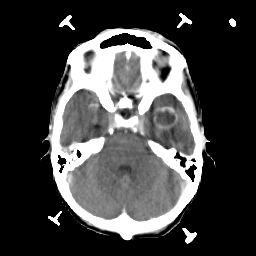

Metastatic bronchogenic carcinoma: Roentgen-ray CT -- Slice #6

[Home][Help][Clinical] Slice 6